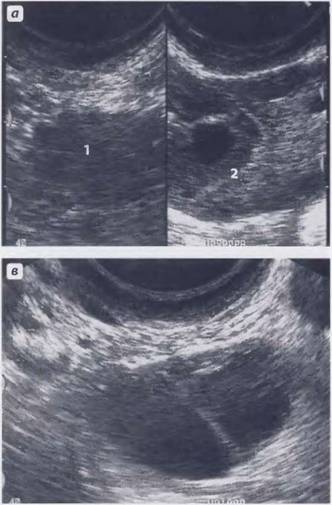

Эти образования хорошо визуализируются при проведении ультразвукового исследования или магнитно-резонансной томографии. Однако во время УЗИ невозможно увидеть ткани, из которых состоит образование, поэтому можно лишь предполагать наличие кальцината. Такая ситуация требует дополнительного обследования женщины, чтобы исключить более серьезные заболевания, чем просто наличие отложений солей кальция.

Одним из наиболее распространенных методов диагностики является ультразвуковое исследование репродуктивных органов. Гинекологи часто рекомендуют трансабдоминальное УЗИ, которое позволяет выявлять патологии органов с помощью датчиков, перемещаемых по животу пациентки.

- трансвагинальное УЗИ, которое обеспечивает более детальное исследование органа, особенно в период беременности;

- трехмерное УЗИ – современный метод диагностики заболеваний матки, который позволяет визуализировать кальцинаты в трехмерном формате;

Уже после дополнительной диагностики станет понятно, является ли это угрозой для репродуктивного здоровья женщины. Часто на обычном УЗИ кальцинаты в детородном органе путают с полипами. Полипы угрожают женщине постоянными кровотечениями и патологиями беременности.